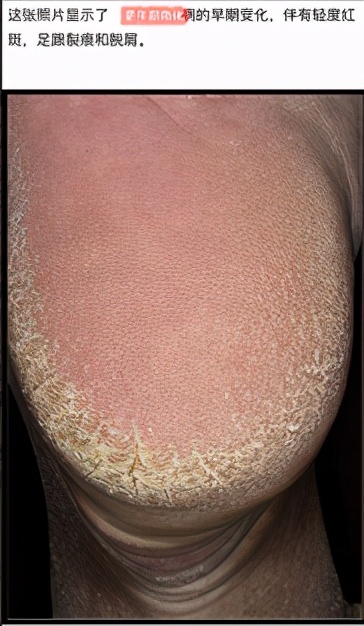

一,更年期角化病疹子是什么样子的?

这种皮肤增厚现象多出现在围更年期和更年期妇女的足部,开始于足后跟缘和足掌的压力处。随着角化增厚的发展,疹子增大、增厚,皲裂。但通常不痒,疼痛也不明显。